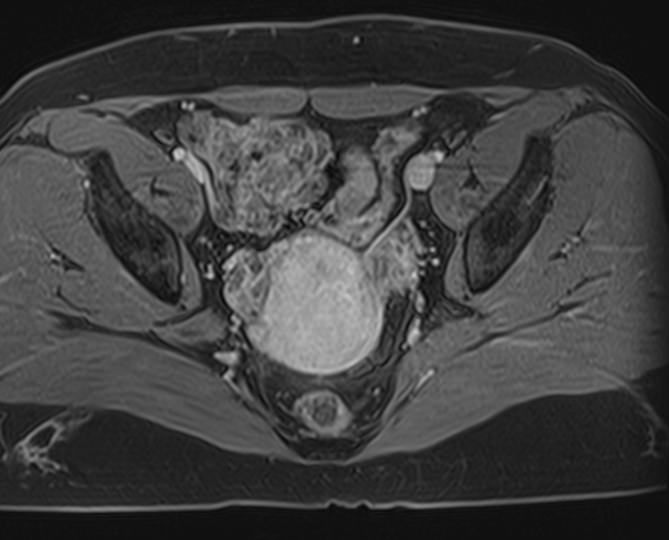

Магнитно-резонансная томография органов малого таза включает в себя исследование женских половых органов (матка, яичники), мужских половых органов (предстательная железа, семенные пузырьки, семявыносящие протоки), мочевого пузыря с мочеточниками, прямой кишки, тазовой брюшины, лимфатических узлов, мягких тканей малого таза.

В нашей клинике исследование выполняется на современном высокопольном томографе экспертного класса TOSHIBA VANTAGE TITAN 1,5 Тесла. Высокая индукция магнитного поля обеспечивает повышенную четкость изображений и превосходную детализацию анатомических структур. Аппарат производит сканирование в трех взаимоперпендикулярных плоскостях и послойными срезами с шагом от 1 мм, что позволяет визуализировать структуру органов и тканей малого таза в мельчайших подробностях.

Инновационные компьютерные программы преобразуют данные, полученные при сканировании, в 3D-изображения исследуемых органов. Методика трехмерной реконструкции используется для улучшения наглядности изображения зоны исследования, тем самым, повышает достоверность диагностики.

Выполнение МРТ малого таза в стандартном режиме возможно без использования контраста. Однако при подозрении на патологические изменения со стороны органов мужской или женской половой сферы, мочевыделительной системы, прямой кишки или окружающих мягких тканей, обязательным является введение контрастного препарата, имеющего в своем составе металл гадолиний. Степень и характер накопления контрастного препарата в органах и тканях позволяет различать патологические процессы, в том числе, диагностировать опухоли. Это используется для диагностики онкологических заболеваний на ранних стадиях, что имеет решающее значение для жизни и здоровья пациента.